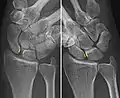

Scapholunate ligament disruption associated with a Colles' fracture

The scapholunate ligament is an intraarticular ligament binding the scaphoid and lunate bones of the wrist together. It is divided into three areas, dorsal, proximal and palmar, with the dorsal segment being the strongest part.[3] It is the main stabilizer of the scaphoid. In contrast to the scapholunate ligament, the lunotriquetral ligament is more prominent on the palmar side.